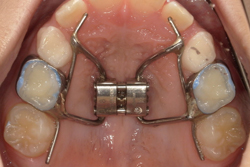

¡Ú¾ÉÎã3¡Û¹ü³Ê¤ÎÀ®Ä¹¥³¥ó¥È¥í¡¼¥ë¤ò¹Ô¤Ã¤¿¾®»ù¶ºÀµ¤Î¾ÉÎã

- ¼£ÎÅÁ°

- ¼£ÎŸå

- ¹ü³Ê¤ÎÀ®Ä¹¥³¥ó¥È¥í¡¼¥ë¤ò¹Ô¤Ã¤¿¾®»ù¶ºÀµ¤Î¾ÉÎã

¼£ÎÅÆâÍÆ

´µ¼ÔÍͤξɾõ

¹ü³ÊŪ¤Ê¼õ¤±¸ý¤Î¾ÉÎã¡¢¾å²¼¤Î»õ¤Ê¤é¤Ó¤Î¥¬¥¿¥¬¥¿¡¢ÆÃ¤Ë¾å¤Î»õ¤Ï¡¢Á°»õ¤È±ü»õ¤È¤ÎÁ°¸åŪ¤Ê¥¹¥Ú¡¼¥¹¤âÉÔ¤·¤Æ¤ª¤ê¡¢Á°»õ¤Î³ú¤ß¹ç¤ï¤»¤âÈ¿ÂÐÒû¹ç¤È¤Ê¤Ã¤Æ¤¤¤Þ¤·¤¿¡£

¼£ÎÅË¡

¹ü³Ê¸ÇÄê¼°¤Î³ÈÂ硦±ó¿´°ÜưÁõÃ֤Ȥ¤¤¦¾å³Ü¤Î¦Êý³ÈÂç¤È¾å¤Î±ü»õ¤ò¸åÊý¤Ëư¤«¤¹¤³¤È¤òƱ»þ¤Ë¹Ô¤¦ÁõÃ֤ȡ¢¥×¥í¥È¥é¥¯¥¿¡¼¤È¤¤¤¦¾å³Ü¡¢Ãæ´éÌ̤ÎÁ°²¼Êý¤Ø¤ÎÀ®Ä¹¤òÂ¥¤¹ÁõÃ֤ȤòÊ»ÍѤ·¡¢À®Ä¹¥³¥ó¥È¥í¡¼¥ë¤ò¹Ô¤¤¤Þ¤·¤¿¡£

ÁõÃ֤ϡ¢¸ý¹ÐÆâ¥¹¥¥ã¥Ê¤Ç¸÷³Ø°õ¾Ý¤·¡¢3D¥×¥ê¥ó¥¿¤Ç¥«¥¹¥¿¥à¥á¥¤¥É¤·¤Þ¤·¤¿¡£ -

¼£ÎÅ·ë²Ì

ÂèI´ü¤Î¶ºÀµ¼£ÎÅ(»Ò¤É¤â¤Î»þ´ü¤Î¶ºÀµ¼£ÎÅ)¤ò½ª¤¨¤Æ¡¢¼õ¤±¸ý¤Î²þÁ±¡¢»õʤӤΥ¬¥¿¥¬¥¿¤Î·Ú¸º¡¢¸ý¸µ¤Î¥Ð¥é¥ó¥¹¤Î²þÁ±¤òǧ¤á¤Þ¤·¤¿¡£

º£¸å¡¢»×½Õ´üÀ®Ä¹´ü¤¬²á¤®¤ë¤Î¤òÂԤäơ¢ÂèII´ü¤Î¶ºÀµ¼£ÎÅ(Âç¿Í¤Î»õ¤òºÇ½ªÅª¤Ëʤ٤뼣ÎÅ)¤ò¹Ô¤¦Í½Äê¤Ç¤¹¡£